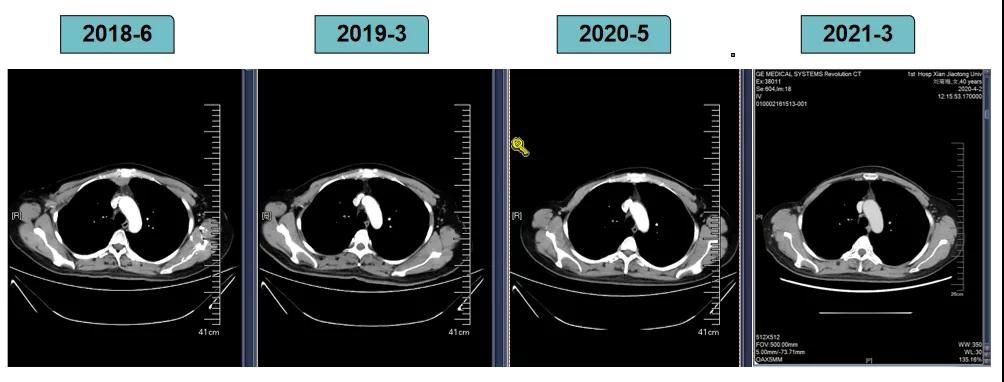

胸腹部增强CT示(2018-6-28):胸骨后占位,肝内异常强化灶,腹膜后肿大淋巴结。

非靶病灶:肝左叶、肝右前叶下段;纵膈胸骨后淋巴结节;前上纵膈淋巴结;腹膜后小淋巴结

影像学评估-纵膈淋巴结: